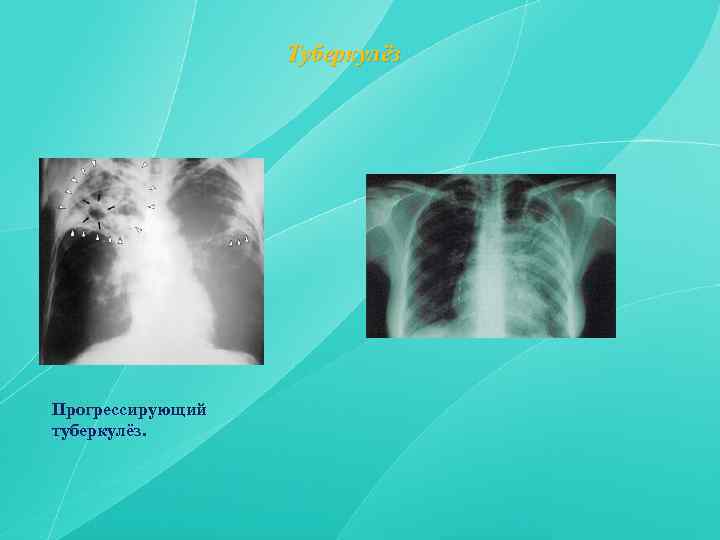

Симптомы и лечение инфильтративного туберкулеза легких

Раздел: Снимки-откровения